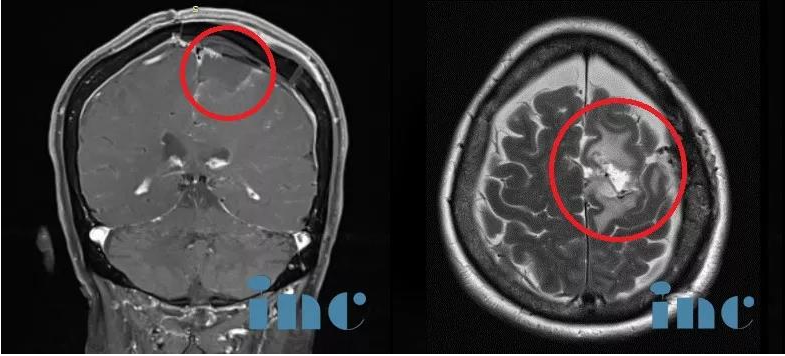

要知道,患者在手术前的6年时间里一直在被大脑里的这个较大镰旁脑膜瘤所苦恼,刚开始症状还不明显,但随着时间的推移,脑膜瘤长的有5cm那么大了,从影像上看像一颗鸡蛋大小。

而在德国INI国际神经学研究所、由INC德国巴特朗菲教授主刀的一场高质量手术直接全部切除了患者大脑深部复杂部位的脑膜瘤,她大脑中的“定时炸弹”被完全摘除。如今手术已过去了1年半,从其术前MR、刚手术后的MR、术后1年半多的MR可以清楚看到未见复发迹象,患者现在生活如常,幸福的晚年生活不必再被可怕的肿瘤打扰。

术前MR

术后MR

术后1年半MR